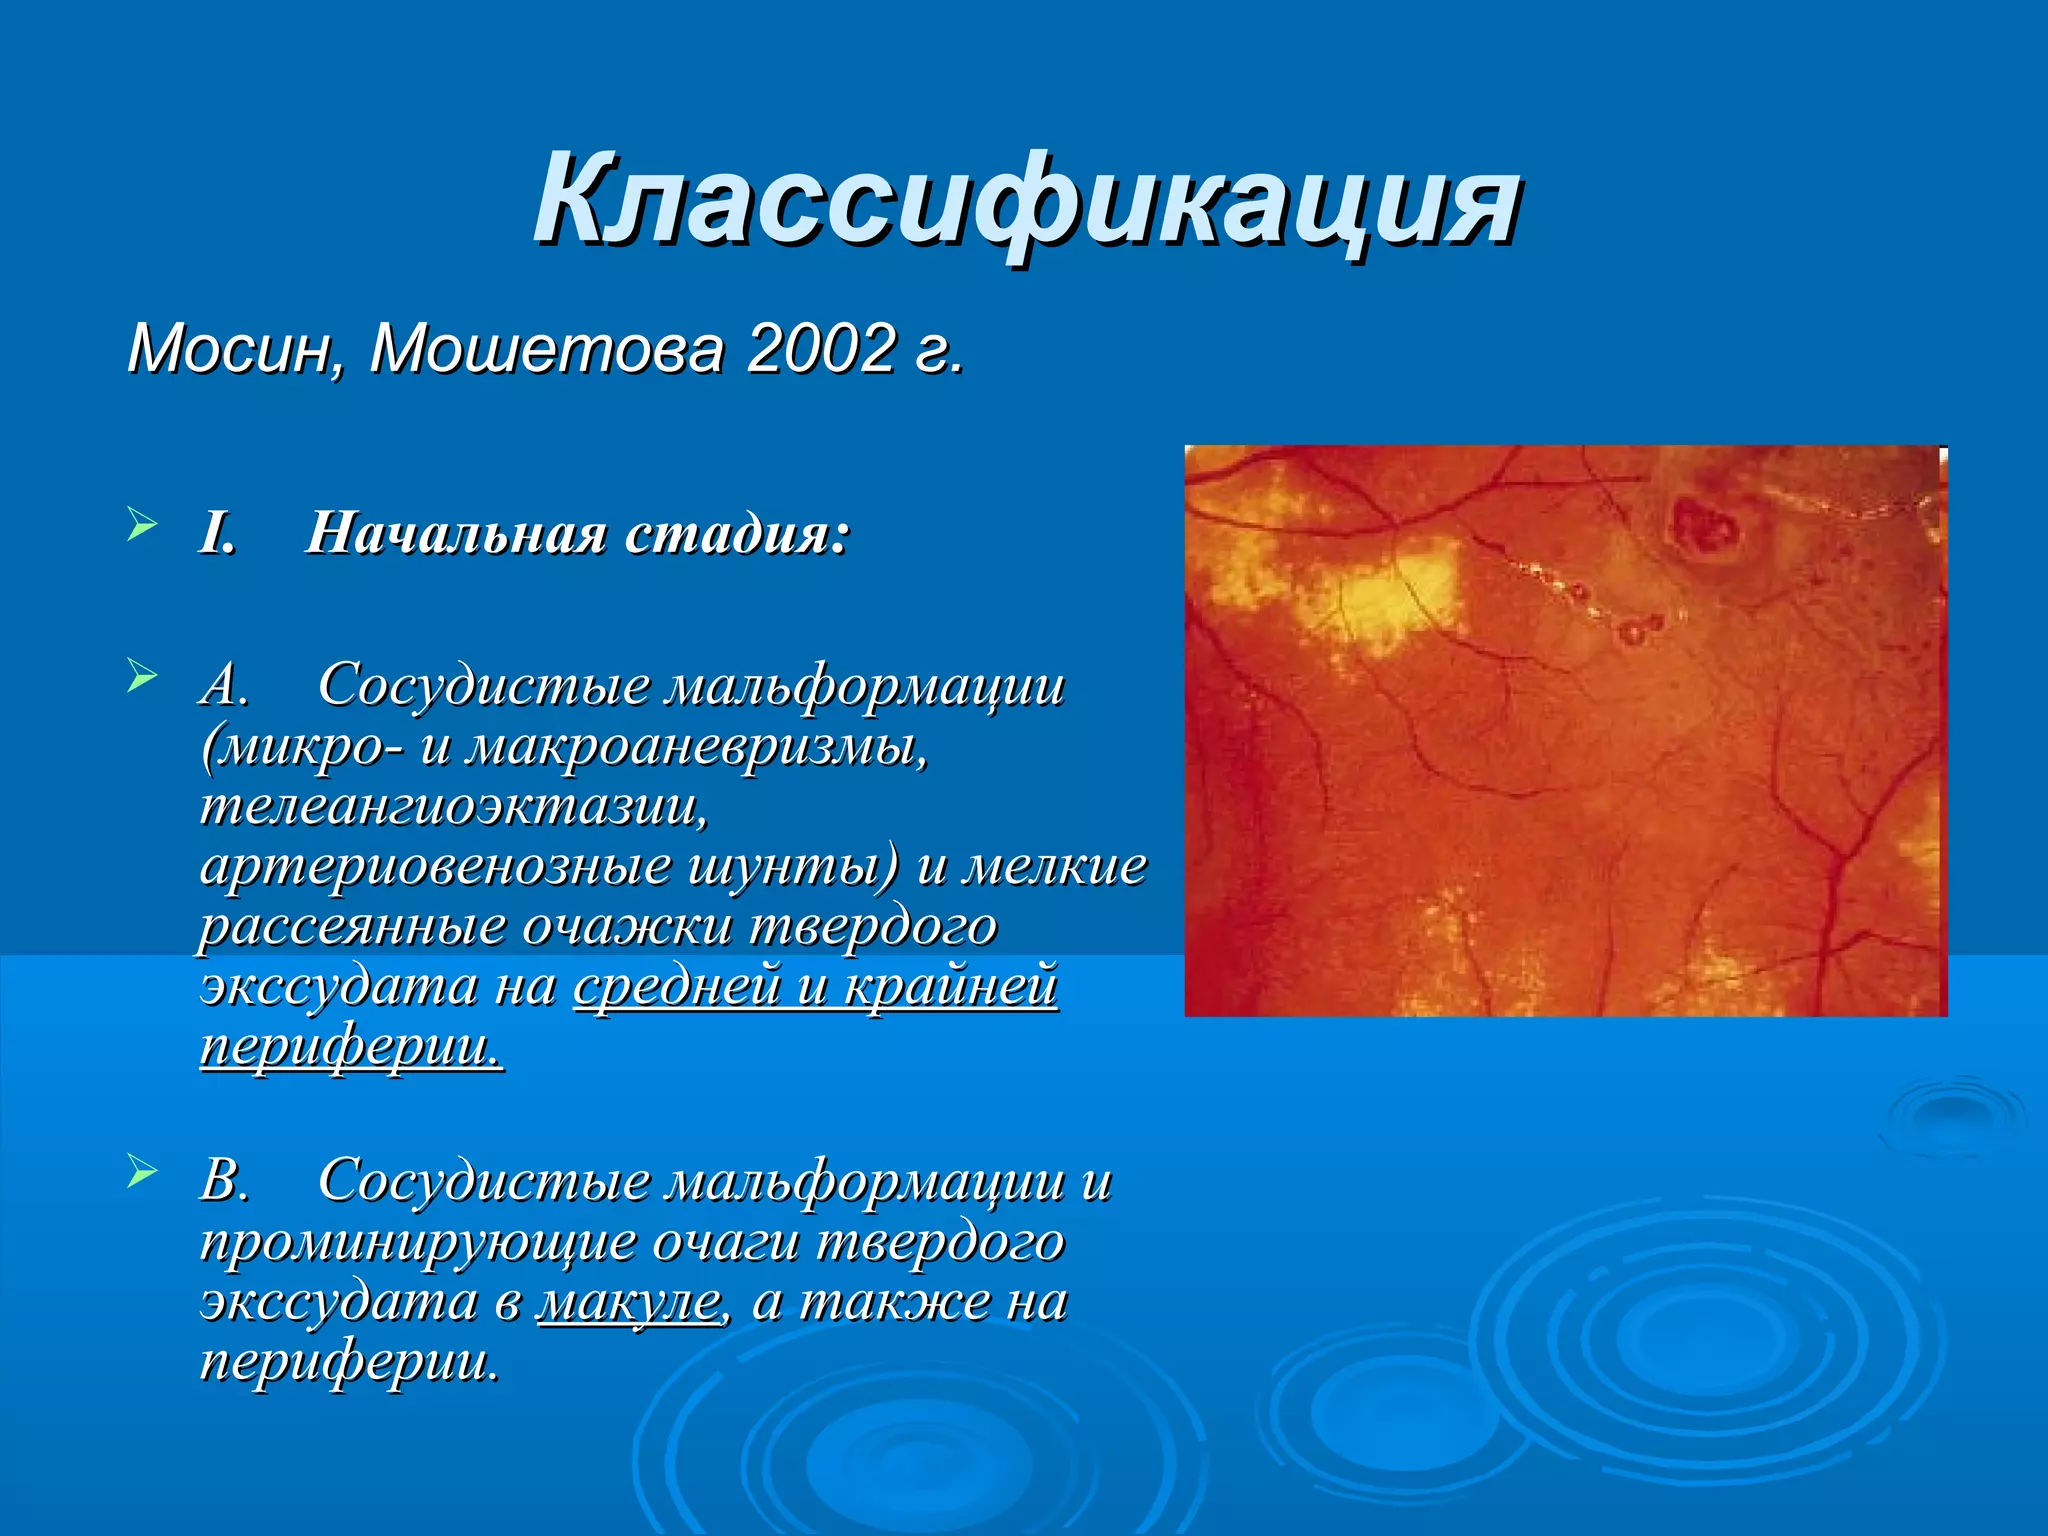

Болезнь Коатса - это идеопатическое заболевание, характеризующееся полиморфными изменениями сосудов сетчатки с массивной экссудацией, чаще всего у детей и подростков, с преобладанием среди мальчиков. Эпидемиология показывает, что заболевание проявляется, как правило, в возрасте 8-16 лет, но возможно его обнаружение и у взрослых. Основные проявления включают ретинальные аномалии, субретинальную экссудацию и постепенно прогрессирующую потерю зрения.